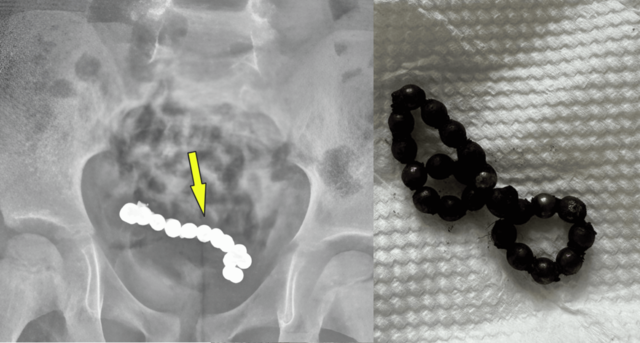

12일 의학저널 ‘큐레우스’에 따르면 오만에서 한 4살 소년이 복통으로 병원에서 복부 CT 검사를 받은 결과, 뱃 속에 동그란 물체가 마치 사슬같은 모양으로 여러 개 붙어 있는 형태의 이물질이 확인됐다.

해당 병원이 복강경 수술을 통해 뱃속에서 22개의 자석을 꺼내는 데 성공했다. 이 자석들은 서로 붙어 있었다.

자석들로 인해 장 일부가 괴사되어 절제하는 수술도 함께 이뤄졌다.